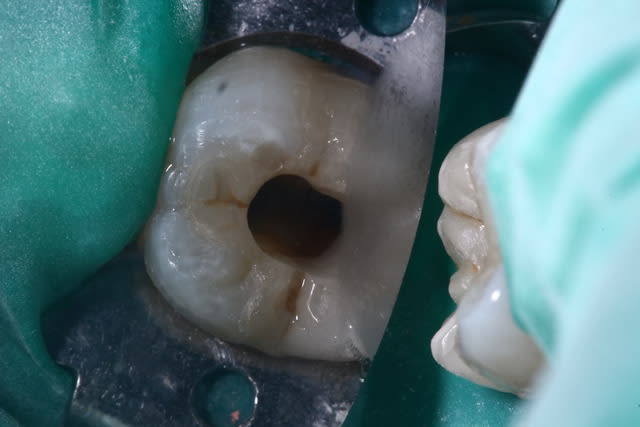

Quand ça arrive, et bien on passe a travers comme si la dent était intacte ...

On fait l'endo et on referme avec un compo.

Est ce que tu es pas mieux pour faire l'endo avec l'onlay en place, qu'en retirant tout ?

L'entrée canalaire est obturée, et l'étanchéité est obtenu au moins 1.5mm autour de l'entrée des canaux.. (CVI en fond de cavité + Compo)